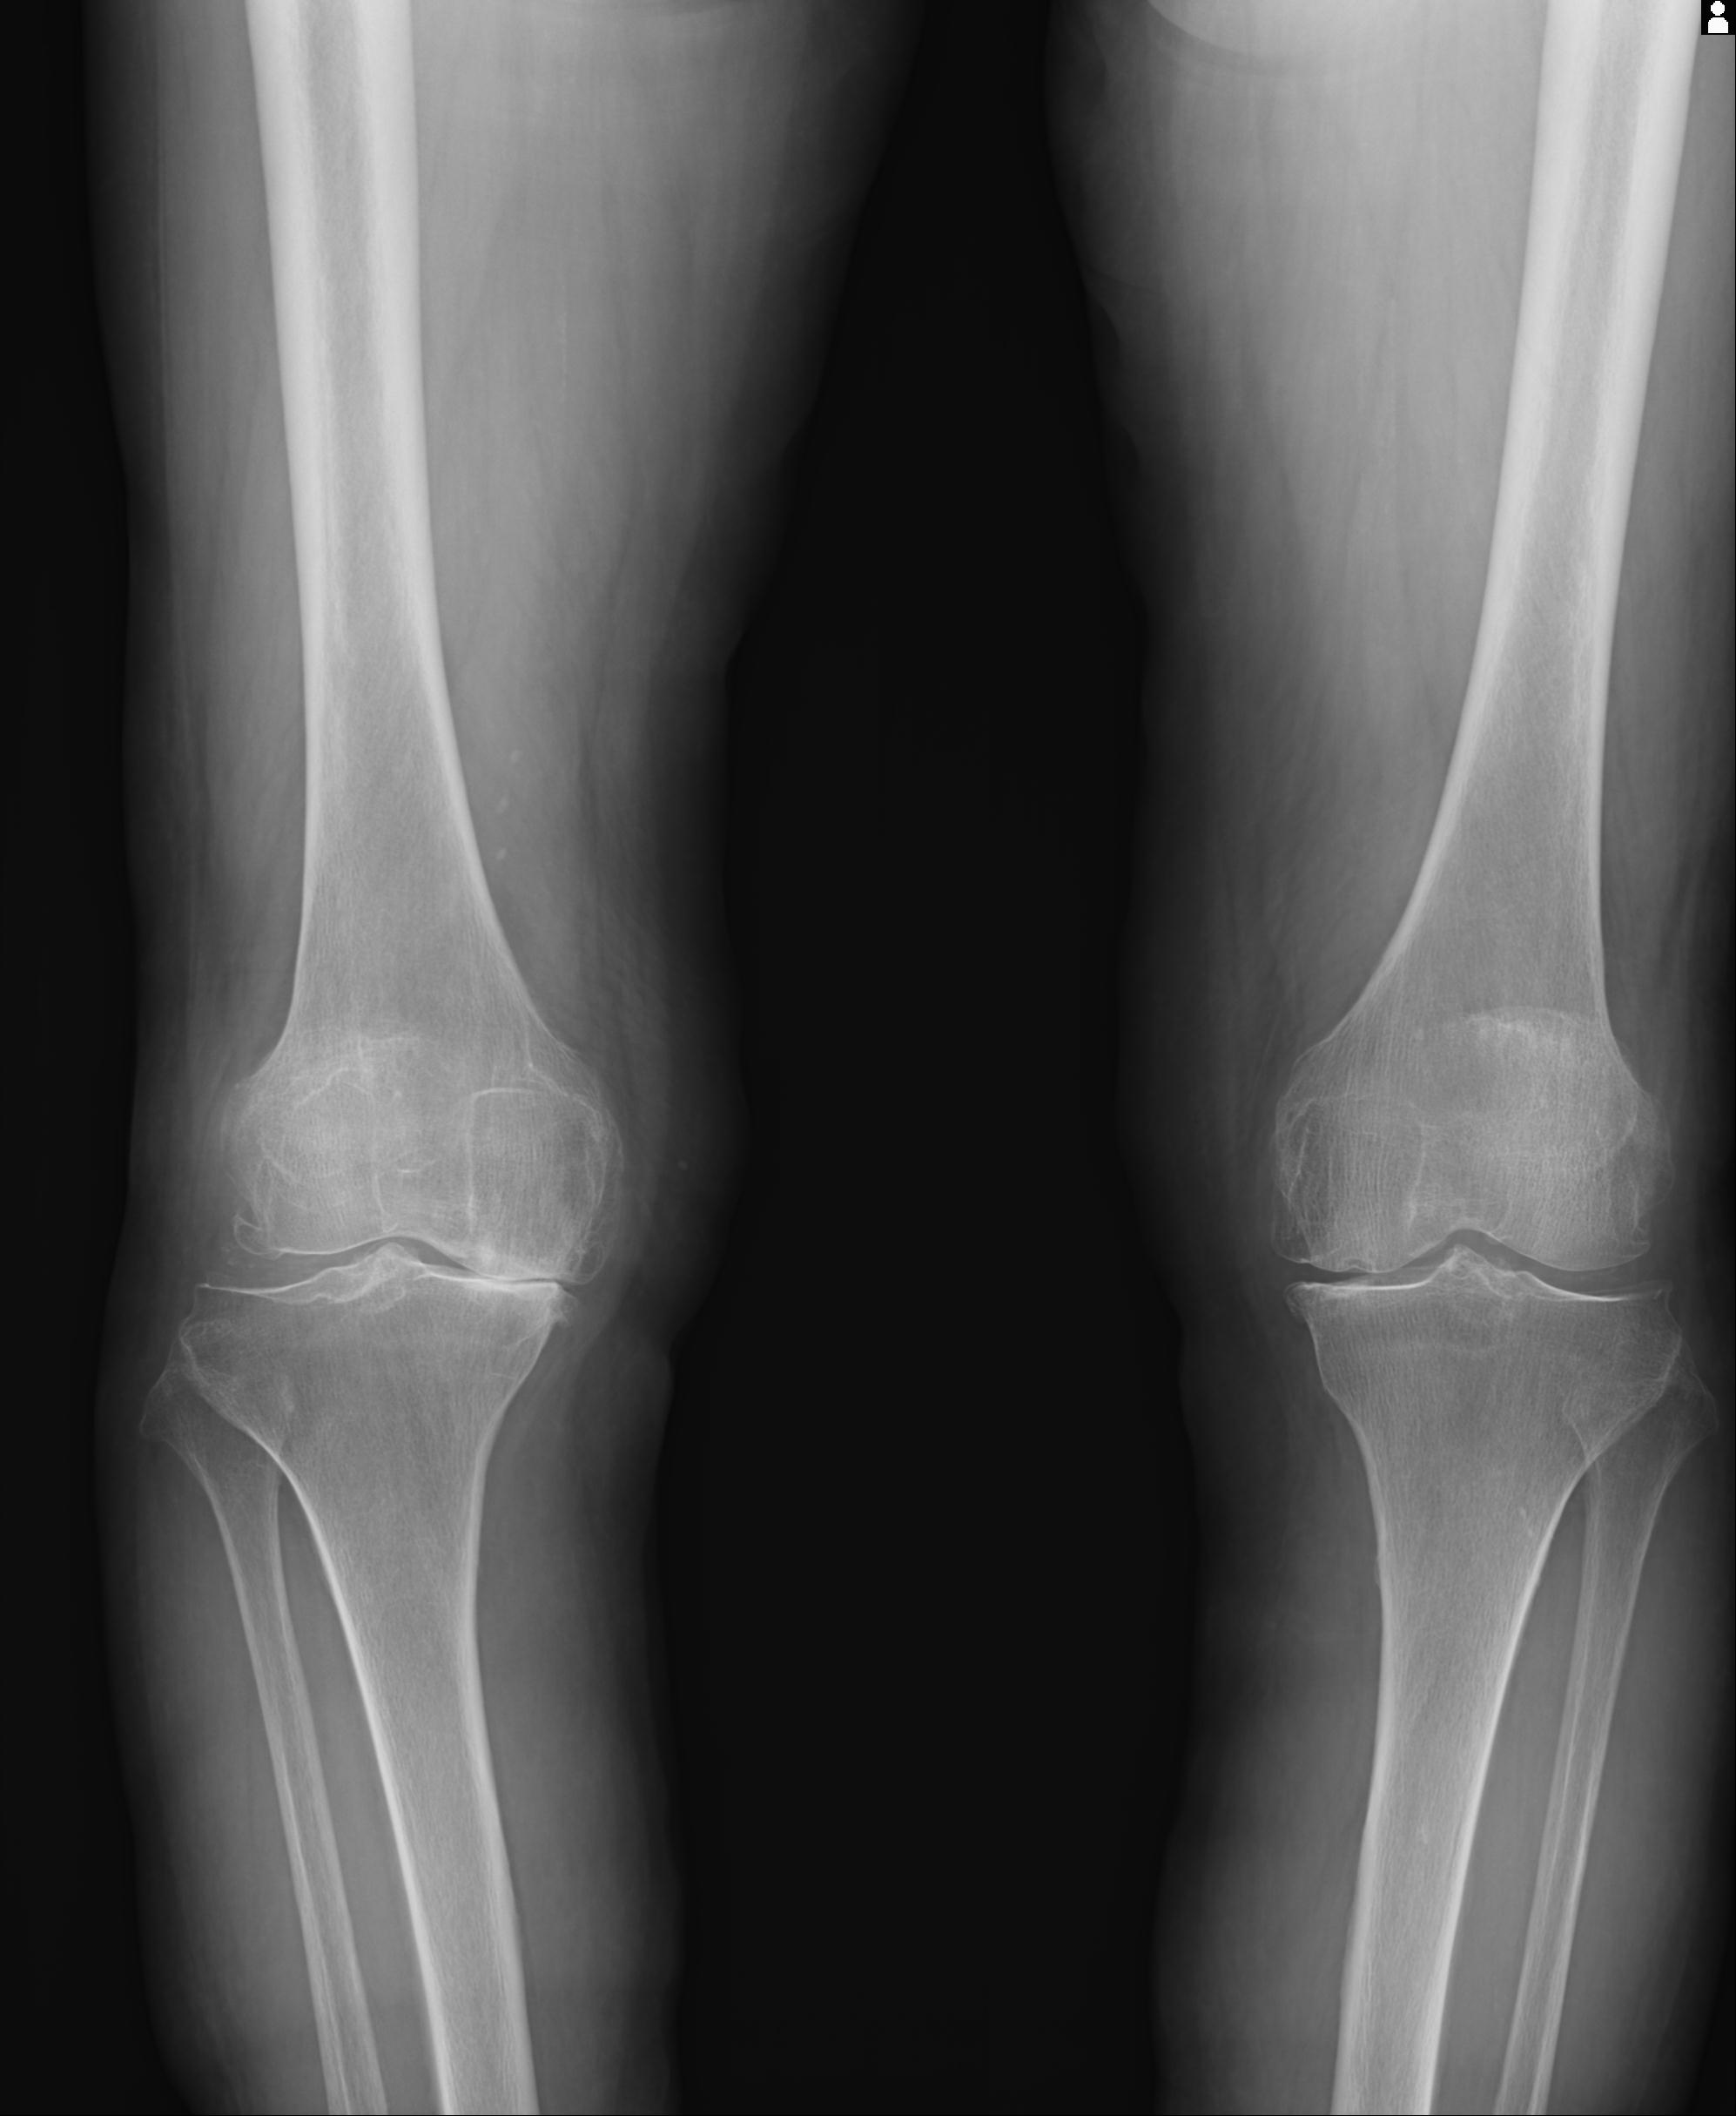

100612 11/25 1/20 右膝 2R 84歳女性 右TKA